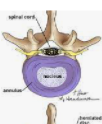

급성으로 오는 허리통증은 금방 회복되지만, 만성적인 허리통증은 대부분의 원인이 추간판 탈출증 입니다. 허리디스크라고 칭하기도 합니다.

또한 척추관이 협착되어 발생하는 것도 흔한 원인중에 하나 입니다.

퇴행성 질환은 척추의 뒷쪽 관절이 퇴행성 변화가 오면서 디스크가 점점 변형이 됩니다.

허리디스크 (추간판탈출증)는 많이 들어보셨을 겁니다.

허리로부터 다리로 뻗어나가는 신경이 저리기 시작하며 전형적인 저린감과 당기는 통증이 발생 합니다.